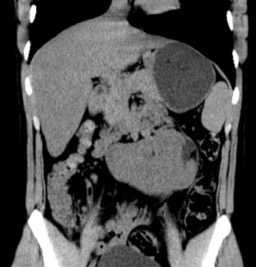

Морфологические аномалии включают подковообразную почку, почку в форме пирога и слияние почек с расположением на одной стороне или по средней линии.

Подковообразная почка встречается чаще других и представляет собой увеличение одного из полюсов почки, в 90% - нижнего. Нередко меняется и положение подковообразной почки, которая может быть смещена медиально или даже на противоположную сторону. Подковообразная почка видна при любом виде исследования - внутривенной урографии , УЗИ, КТ, МРТ почек или сцинтиграфии.

Подковообразная почка

Подковообразная почка - это врожденная аномалия, при которой обе почки сращиваются между собой в области нижнего или верхнего полюса с образованием перешейка. Патология часто осложняется пиелонефритом, мочекаменной болезнью, гидронефрозом и другими заболеваниями мочевыделительной системы. В используется УЗИ, урография, пиелография, компьютерная томография почек. Хирургическое лечение показано при развитии в измененной почке урологического заболевания, требующего оперативной тактики.

Подковообразная почка встречается в современной урологии с частотой 10-15% от всех почечных аномалий, в соотношении 1 случай на 500 новорожденных, причем у мальчиков в 2,5 раза чаще, чем у девочек. Порок характеризуется сращением почек в области нижних, реже - верхних полюсов, в результате чего соединенные почки приобретают «U»-образный вид, напоминающий подкову. При этом каждая из почек имеет свой мочеточник, впадающий в мочевой пузырь, и питающие сосуды. В 88,6% подковообразные почки имеют аномальное кровообращение и необычное строение чашечек.